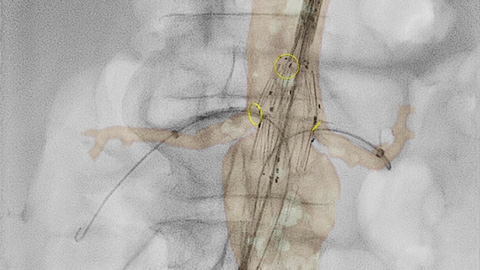

Ofrecemos una gama de herramientas clínicas avanzadas, como VesselNavigator, EchoNavigator y HeartNavigator para la orientación por imágenes 3D en vivo. Nuestra exclusiva Dynamic Coronary Roadmap (hoja de ruta coronaria dinámica) le ayuda a navegar por las arterias tortuosas de manera eficiente y precisa. Cada disciplina quirúrgica puede beneficiarse de herramientas avanzadas de fusión de imágenes que pueden mejorar la confianza, la eficiencia y la precisión durante los procedimientos.

SmartCT* le proporciona imágenes similares a las de la TC lo que le permite hacer mediciones y visualizaciones avanzadas en la pantalla táctil en la mesa, para estudiar el tipo y la extensión de la enfermedad con gran detalle. Las imágenes 3D de SmartCT* pueden ayudar a revelar información no aparente en las imágenes 2D o de la DSA. Esta información adicional puede cambiar el diagnóstico, la planificación del tratamiento o la administración del tratamiento, lo que respalda un mejor resultado para el paciente.17-19

A través de la herramienta del marcador en la pantalla táctil, puede señalar un área de interés en las imágenes 2D. Las marcas se muestran con claridad en la fluoroscopia y las imágenes de referencia, y se escalan y desplazan con la imagen. Esto puede ser útil para marcar una bifurcación, ramas laterales y otros detalles relevantes. Con la herramienta del marcador, no hay necesidad de una aplicación de marcador independiente en el laboratorio.